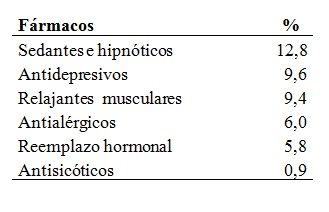

Se relevó la cantidad de pacientes que recibían en forma permanente medicación con posible efecto sobre el sistema de control de la respiración. Se incluyeron: sedantes e hipnóticos, antidepresivos, relajantes musculares, antialérgicos, hormonas de reemplazo y antisicóticos (Tabla 8).

Tabla 8: Tratamientos farmacológicos

Tabla 8. Frecuencia pacientes que recibían fármacos relevados (n=447).